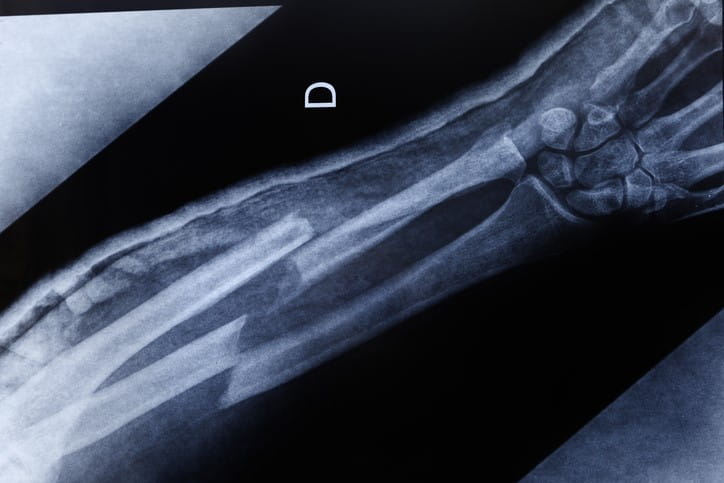

The standard way to diagnose fractures is through x-rays.

X-rays give a clear image of the bone. They can show where the break is and what type of break it is. Doctors who have trained to read X-rays can even spot tiny breaks on an X-ray.

But X-rays don't show soft tissues, like ligaments, tendons, or cartilage. They also can't show blood vessels or nerves. If your doctor thinks you might have other injuries related to the fracture, you may need an MRI.